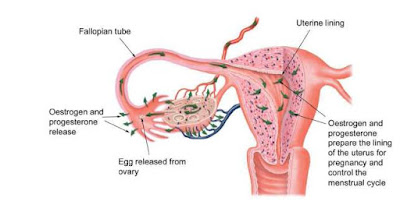

Hormones are the hallmark of the endocrine (endo = within, and crine = sift) system. When released into the bloodstream, they travel to every part of the body so that all cells have the opportunity to respond. Not all will, and you wouldn’t want them to. Specific cells and organs have the ability to respond to specific signals because they have the right hormone receptors.

There are eight endocrine glands in a human body. The adrenal glands (2 of them), the parathyroid glands (4), the thyroid gland (1), the pineal gland, the pancreas, the ovaries (2) or testes (2), the hypothalamus, and the pituitary gland. They can be stimulated to release hormones by either neurons, other hormones, or other chemicals. Besides these well known glands, a few tissues will release hormones in specific situations. The placenta will release progesterone and estrogen, and the stomach can release gastrin to stimulate gastric juice (acid) and ghrelin to stimulate hunger.